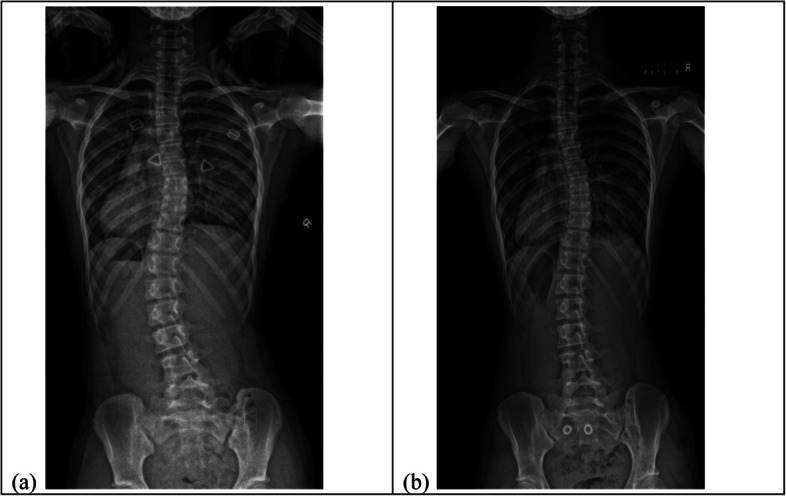

Background: Changes in coronal curve type and curve span may be linked to spinal and rib cage deformities. Therefore, it is crucial to comprehend the potential impact of these changes on brace treatment. This study aims to investigate the relationship between curve progression and change in coronal curve type and curve span in braced patients, and to compare the coronal balance and change in apical vertebral between patients with and without curve pattern change.

Methods: Two hundred seventeen patients who fulfilled the Scoliosis Research Society brace referral criteria were recruited. Radiographs at prebrace and brace weaning were assessed. Patients were classified into three groups based on the curve pattern at prebrace: major thoracic (MT), major lumbar (ML) and double major (DM). Change in coronal curve referred to curve of the greatest magnitude changes from thoracic to lumbar or vice versa. Change in curve span defined as change of at least two vertebral levels in the end vertebra of the curve. Change in apical vertebrae referred to change of at least one vertebral level. The association between coronal imbalance, major curve progression and regression, change in coronal curve type, change in curve span, change in apical vertebrae, and curve type were studied using Chi-square test. Multivariable logistic regression was used to predict curve progression at brace wean in each curve type.

Results: The major lumbar group exhibited a higher risk of coronal imbalance (Listing-MT: 5.6% vs ML: 37.7% vs DM: 23.5%, p < 0.001 and truncal shift-MT: 6.9% vs ML: 27.3% vs DM: 2.9%, p < 0.001) and changes in apical vertebrae (MT: 30.6% vs ML: 58.4% vs DM: 45.6%, p = 0.003). The double major group had a greater likelihood of experiencing changes in the coronal curve type (MT: 0% vs ML: 15.6% vs DM: 25%, p < 0.001) and major curve progression (MT: 23.6% vs ML: 22.1% vs DM: 52.9%, p < 0.001). In the major thoracic group, predictive factors for curve progression included being female, having poor brace compliance, and no change in curve span. However, no significant relationships were found for the major lumbar group. Patients with a larger prebrace major Cobb angle, larger thoracic kyphosis and poor brace compliance from double major group were more likely to experience curve progression.

Conclusions: This study suggests that each curve type undergoes distinct changes during bracing. Future studies should consider the influence of curve type in study design and address the challenges associated with each type.